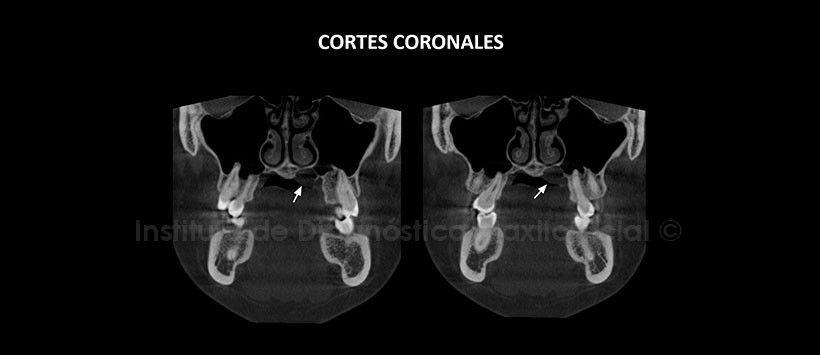

A la evaluación de la tomografía volumétrica (CBCT) mediante cortes axiales (Figura 2), coronales (Figura 3), sagitales (Figura 4), se evidencia una lesión hipodensa de límites definidos, bordes corticalizados, localizado en el lado izquierdo del tercio medio del paladar duro. La lesión ocasiona desplazamiento y adelgazamiento del piso de fosa nasal, así como del contorno medio basal del seno maxilar, se aprecia además un aumento del tejido blando adyacente